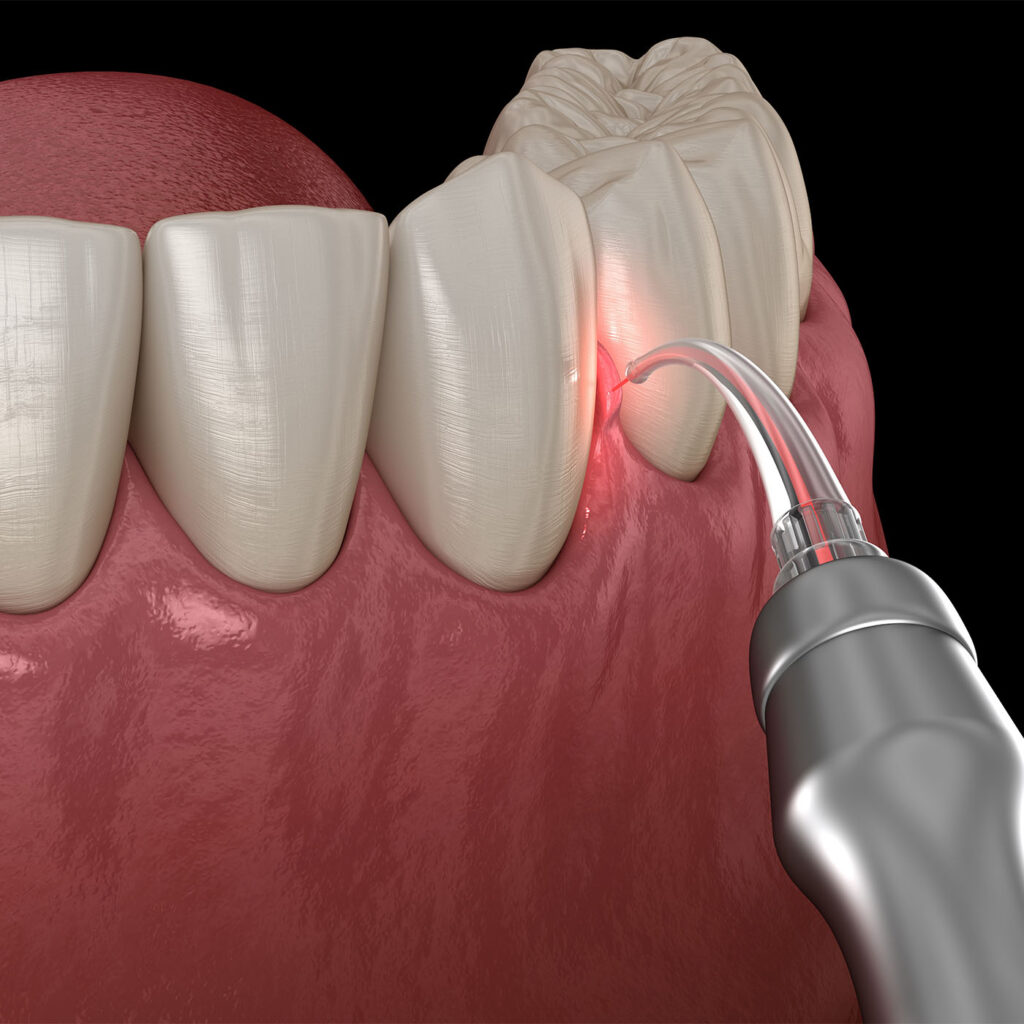

Unlike traditional treatment techniques, Laser technology provides powerful beams of light that sculpt, disinfect, and remove diseased and/or sore areas of the mouth, improving your oral care almost immediately.

- Sculpting and removal of diseased gum tissue

- Deep cleansing Disruption and Disinfection of very damaging bacteria existing in Gum pockets without impact on your healthy tissue

- Abscessed tooth care